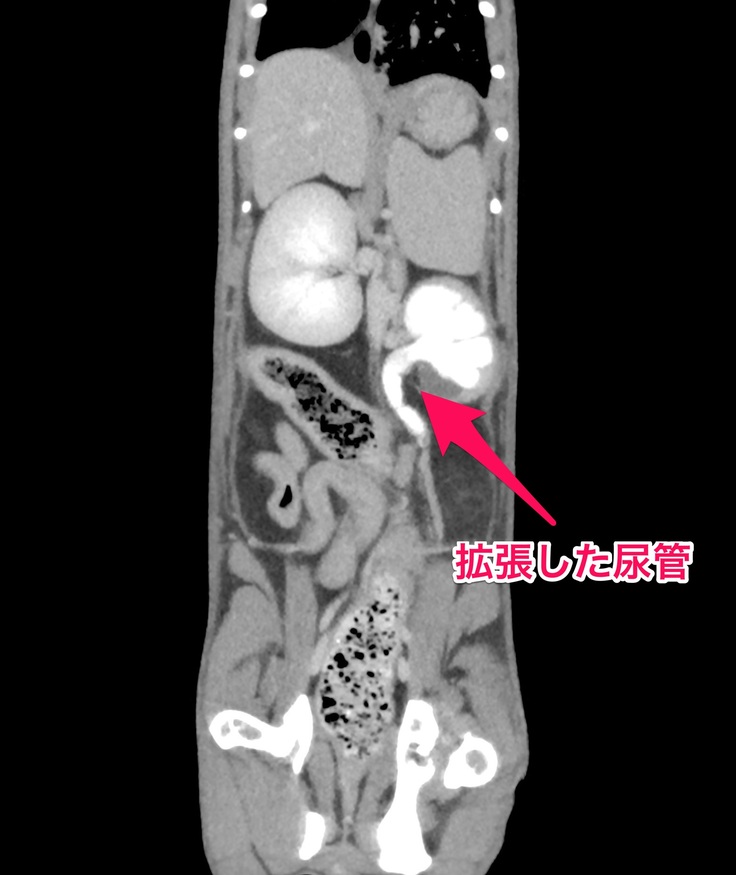

🐈CT検査とエコー検査でも左側の腎臓と腎盂の肥大、尿管のどこかが詰まっているためにおしっこが流れていかずに拡張した尿管が確認されました🐈

今は右側の腎臓と腎盂機能が正常で、機能していない左側の腎臓の分までカバーしてくれているので血液検査でも異常な数値は出なかったけど、右の方も左側と同じように詰まってしまえば腎臓の機能がストップしてしまうので尿毒症や腎不全になったりして食欲不振や嘔吐するようになって体調が良くない日が多くなったり、透析等の別の治療が必要になる場合もあるかなと説明を受けました。